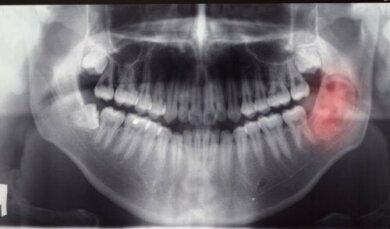

Per analizzare nel migliore dei modi le formazioni mandibolari, verranno prescritti esami diagnostici come radiografie, TAC e ortopantomografia.